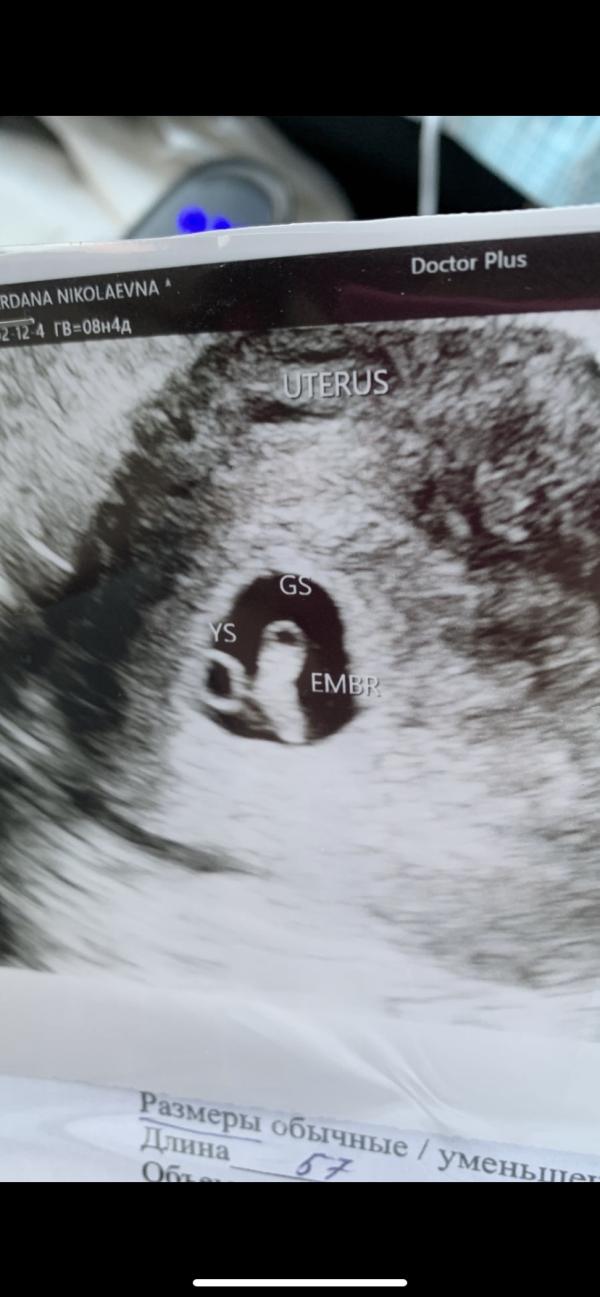

12февр сходила к Крутиковой в Доктор+

Срок также не соответствует, так как возможно была поздняя овуляция( цикл 32-45 дней)

Срок по УЗИ 7нед1день. ЧСС 149. Сказала развивающаяся беременность,но плодное яйцо не соответствует сроку.( сказала что к 1 скрининга видно будет) Я была очень рада, но…..